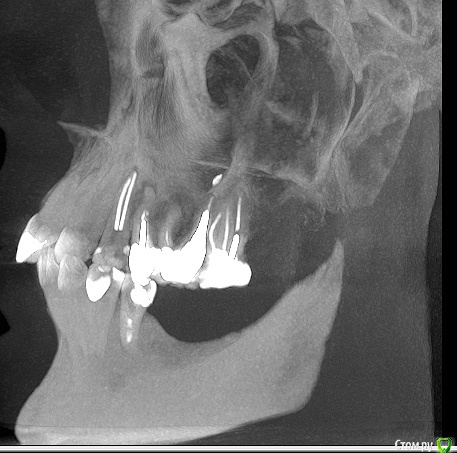

Clearr Опубликовано 9 июля, 2015 Автор Поделиться Опубликовано 9 июля, 2015 Спасибо за отзыв. еще один снимок в другой проекции. есть ли киста на 7 зубе? Ссылка на комментарий

Bier Опубликовано 9 июля, 2015 Поделиться Опубликовано 9 июля, 2015 Эта проекция не предназначена для диагностики состояния зубов Ссылка на комментарий